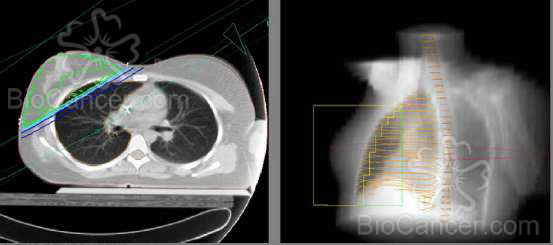

Figura 1. Campos de radioterapia. 50 GY en enfermedad

subclínica y 70 GY en enfermedad clínica